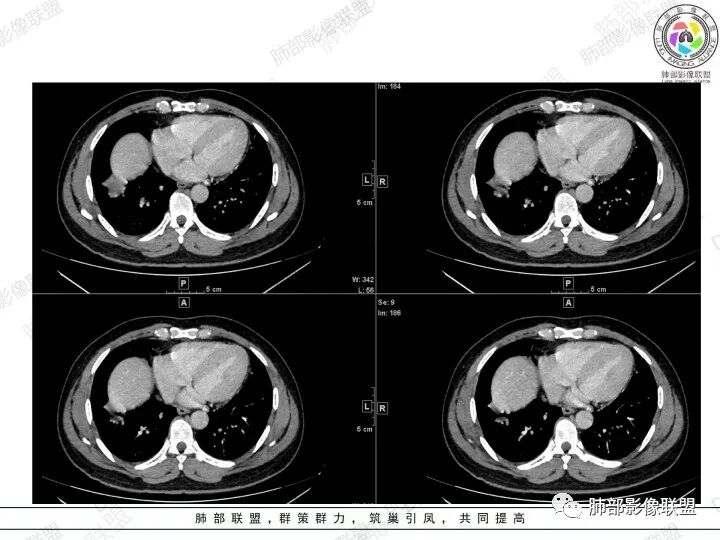

2、胸部CT右肺下叶胸膜下肿块性病变,边缘可见分叶毛刺、边缘膨隆,似有指状凸起,邻近胸膜稍牵拉凹陷,叶间裂以为不明显,提示收缩力较弱。近端支气管进入后截断,病灶内密度尚均匀,增强后可见轻度强化,未见空洞或钙化,并可见血管影进入。右侧肺门及纵隔内可见肿大淋巴结影。无胸腔积液。

3、综合患者临床症状及影像表现,需要考虑肿瘤性病变和非肿瘤性病变,肿瘤性病变需要考虑普通浸润性腺癌或结节型粘液腺癌、淋巴瘤、淋巴上皮瘤样癌、小细胞肺癌等,非肿瘤性病变主要考虑肺脑同病中的隐球菌。①普通浸润性腺癌,以肺外周多年、混合磨玻璃或实性结节/肿块,多见分叶、毛刺、胸膜凹陷、血管集束等征象,本例收缩力较弱、且强化偏轻,不够典型。②粘液腺癌,腺癌的特殊类型。多位于胸膜下(90%位于胸膜下,70%位于下叶胸膜下),边缘清或不清的GGO:提示粘液外渗,少数为纯GGO,缺乏中心纤维化区:毛刺、胸膜凹陷征少,很少胸膜侵犯,淋巴结转移少见,增强后无强化或低强化,本例病灶位于胸膜下,强化轻,收缩力弱,结节期粘液腺癌确实可以符合。③小细胞肺癌,吸烟男性多见,典型征象包括娘小崽大、腊肠样凸起、冰冻纵膈等,本例胸膜下病变大、但肺门淋巴结肿大程度较轻,不符合常见小细胞癌生物学行为,但有可疑指状凸起,小细胞肺癌不能完全除外。④淋巴上皮瘤样癌,少见的恶性肿瘤,患病年龄较轻,肿瘤多位于胸膜下,边缘多光滑,病灶周围可见磨玻璃,毛刺及分叶、胸膜凹陷少见,近端支气管可截断,增强多为中度-明显强化,本例除了强化程度偏轻外,影像表现基本可符合。⑤淋巴瘤,原发肺内淋巴瘤较少见,病灶多位于支气管血管束周围或胸膜下,密度多较均匀,边缘可膨隆也可平直收缩,可见支气管充气征、血管造影征等,强化多为轻中度,本例肺内结节血管穿行自然,局部有血管漂浮,长轴与支气管走行基本一致,肺门淋巴结肿大,不能排除。⑥隐球菌,影像表现可分为孤立结节型、大片实变型、多发结节或实变型、弥漫型。病变多位于胸膜下,边缘平直为主、可伴晕征,可见支气管穿行、部分可见支气管截断,密度多较均匀,部分可伴空洞,增强多为轻中度强化、延迟强化。本例病变位于胸膜下,收缩力弱,强化程度轻,但没有呼吸道症状,病变近端支气管截断,肺门淋巴结大,这些征象都难以用隐球菌解释,基本排除。